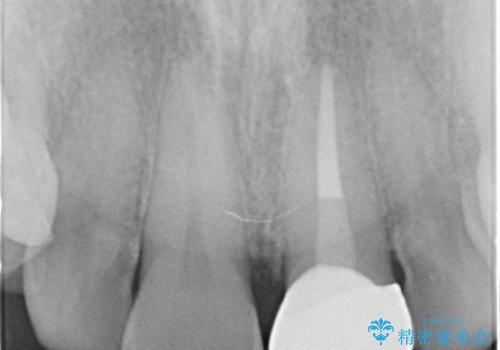

- 前歯の変色を主訴に来院された患者様です。

根管治療からのやり直しをした後、ジルコニアクラウンで色調の改善をしていきます。

- 左上1:根管治療(リトリートメント・前歯)/99,000円 ファイバーコア/22,000円 仮歯/11,000円 ジルコニアクラウン(スタンダード)/121,000円 合計253,000円費用は治療当時の料金となります

歯の黒ずみを完全に見えなくすることができ、大変喜んでいただけました。

被せ物を装着する際は、歯の中(根管)から綺麗にすることも重要となります。